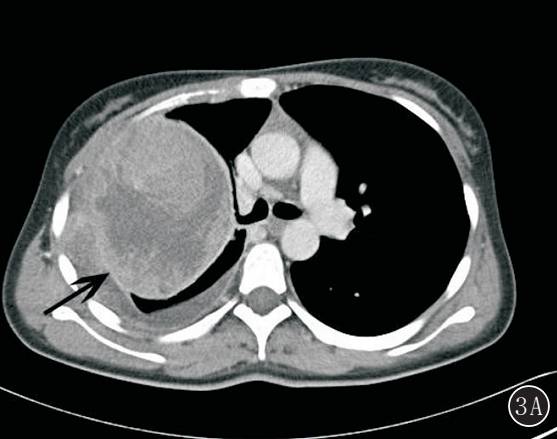

图 3A,B 右上肺滑膜肉瘤。 A. 增强后肿块边缘可见强化的包膜,内部见低密度坏死区,肿块与邻近的胸膜组织粘连,伴右侧胸腔积液;B. 梭形细胞相对较小,细胞密度较高,较一致,核染色细腻(HE ×100)